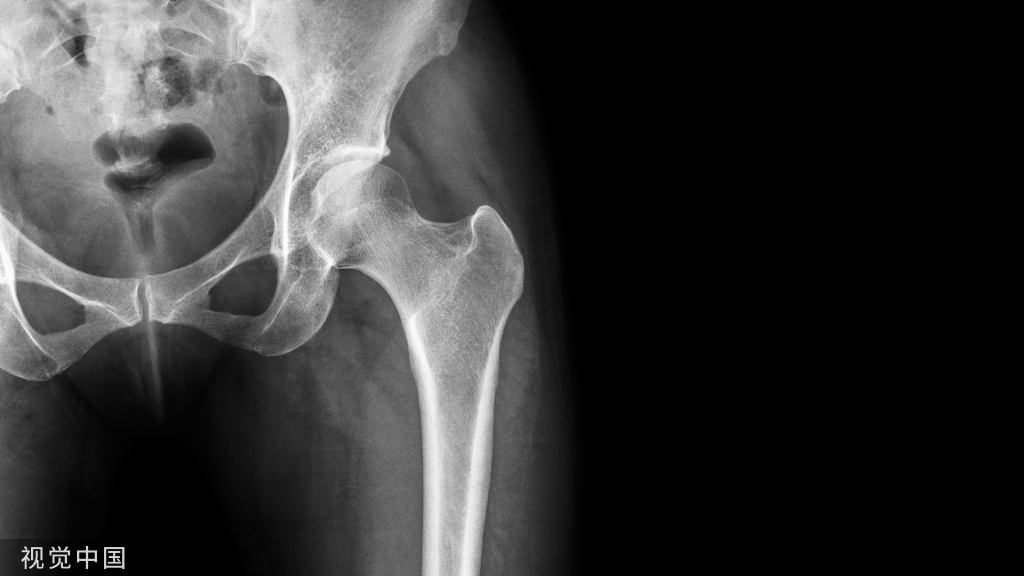

冬天雪后滑倒后,桡骨远端骨折是比较常见的骨折,闭合复位克氏针内固定是较常见的治疗方法,本文参考K-Wiring Principles and Techniques,介绍闭合穿针的手术技巧。